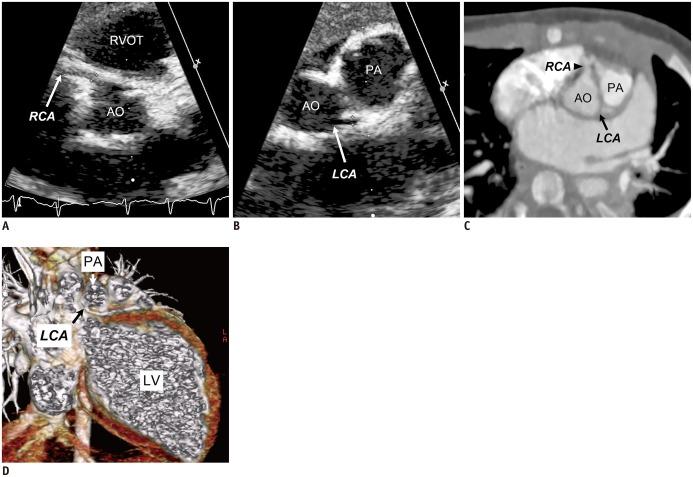

Coronary artery problems in children usually have a significant impact on both short-term and long-term outcomes. Early and accurate diagnosis, therefore, is crucial but technically challenging due to the small size of the coronary artery, high heart rates, and limited cooperation of children. Coronary artery visibility on CT and MRI in children is considerably improved with recent technical advancements. Consequently, CT and MRI are increasingly used for evaluating various congenital and acquired coronary artery abnormalities in children, such as coronary artery anomalies, aberrant coronary artery anatomy specific to congenital heart disease, Kawasaki disease, Williams syndrome, and cardiac allograft vasculopathy.